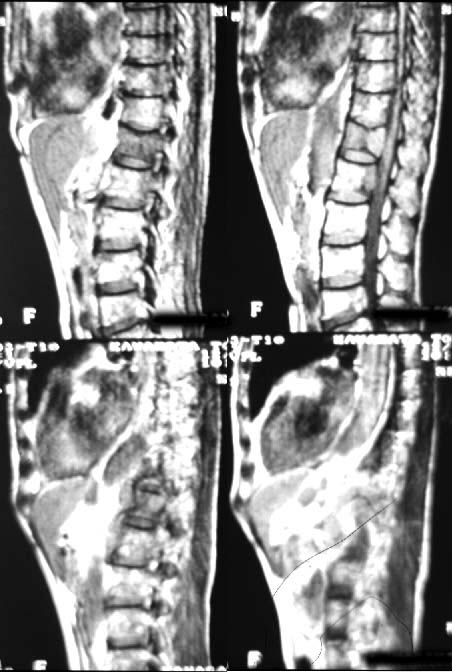

| 第196回定例研究会(1997.6) 骨シンチ『異常集積の少ない骨転移』 | 神奈川県立がんセンター | 小野 慈 |

(2)compartment解析に関しては代表的なものは、1-compartment model(秀毛らの非線形model(Fig.3)に始まるが、篠原が報告した如く線形modelでの短時間に演算可能な方法でも実用的であった。Veraらが唱えた3-compartment modelは採血を伴うmodel式を利用しており、やや煩雑さを伴っている。河らが提唱した5-compartment modelは複雑な計算式を必要としているが、肝最大除去率(Rmax)を算出可能である。(Fig.4)病的 hotなし。 | 第12胸椎に骨溶解像。 | 第12胸椎に 低信号域。 |

![]() | ![]() | ![]() |